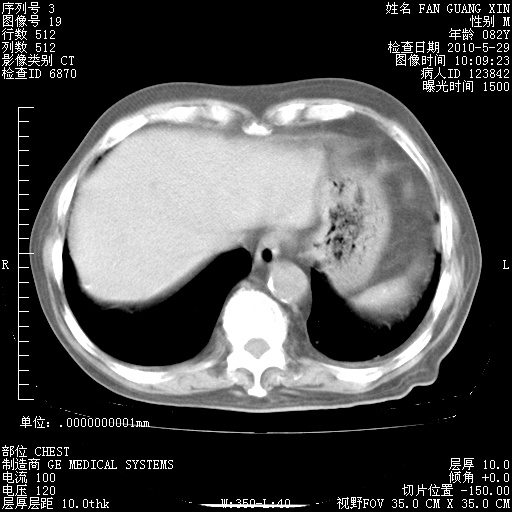

再治疗10天后的肺部CT

阅读此次胸部CT,肺间质渗出性改变较入院时有吸收。目前从体温、白细胞、中性分叶明显增高,肯定存在细菌感染(发生医院感染哦,若无消化道及泌尿系统等感染的依据,肺部感染可能大)。若你院头孢哌酮舒巴坦钠耐药率较高,同意你的方案,若48小时体温仍高,可考虑使用碳青霉稀类抗菌药物,同时可予超声雾化、注意滴数时加大液体量。白蛋白33.30g/L较低哦,需加强营养等支持治疗。